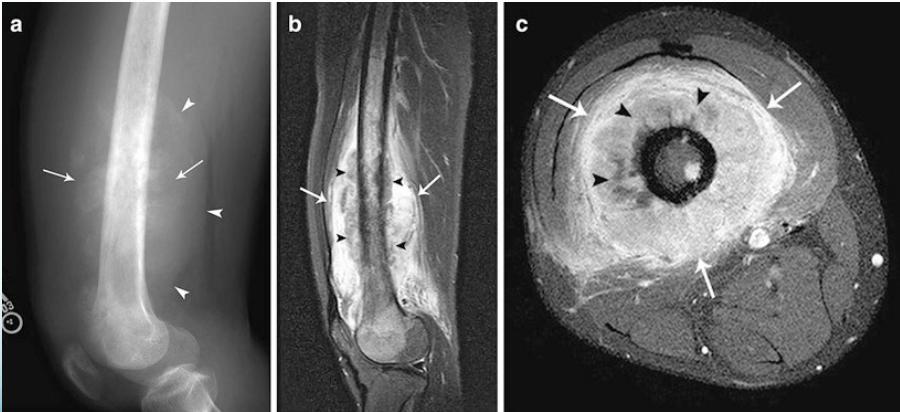

Radiological Features

- X-ray:

- Diaphyseal

- Bone destruction

- New bone formation:

- Along the bone

- “Onion-peel” layers

- ? “Sun-ray”

- ? Codman’s triangle

- Secondaries – in skeleton